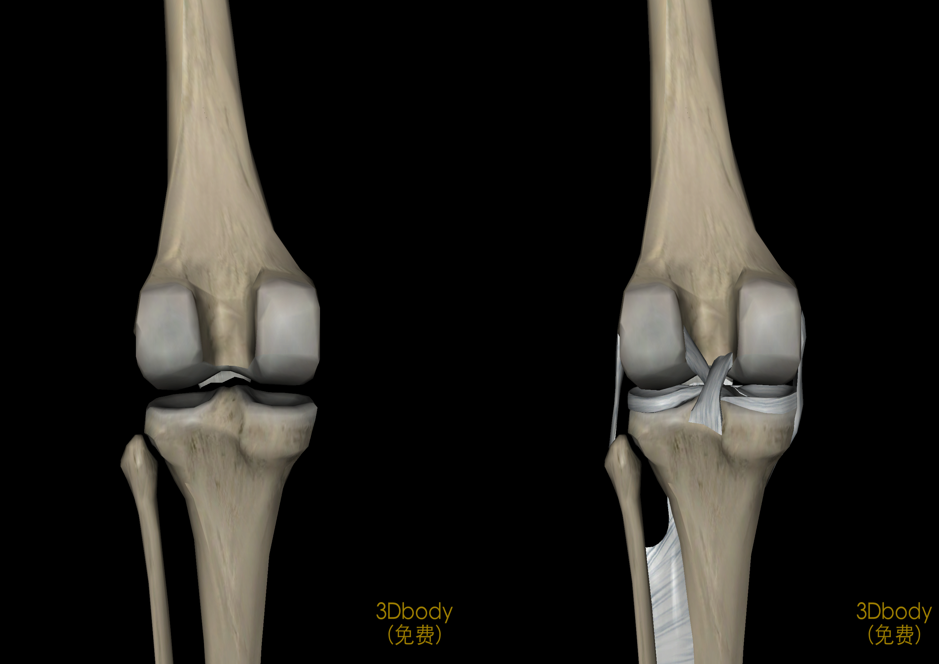

膝关节解剖

病因和发病机制关节的基本结构:关节面、关节软骨、关节腔、关节囊关节软骨:厚度约为2-7mm软骨表面光滑,摩擦系数很小,故有利于关节活动。